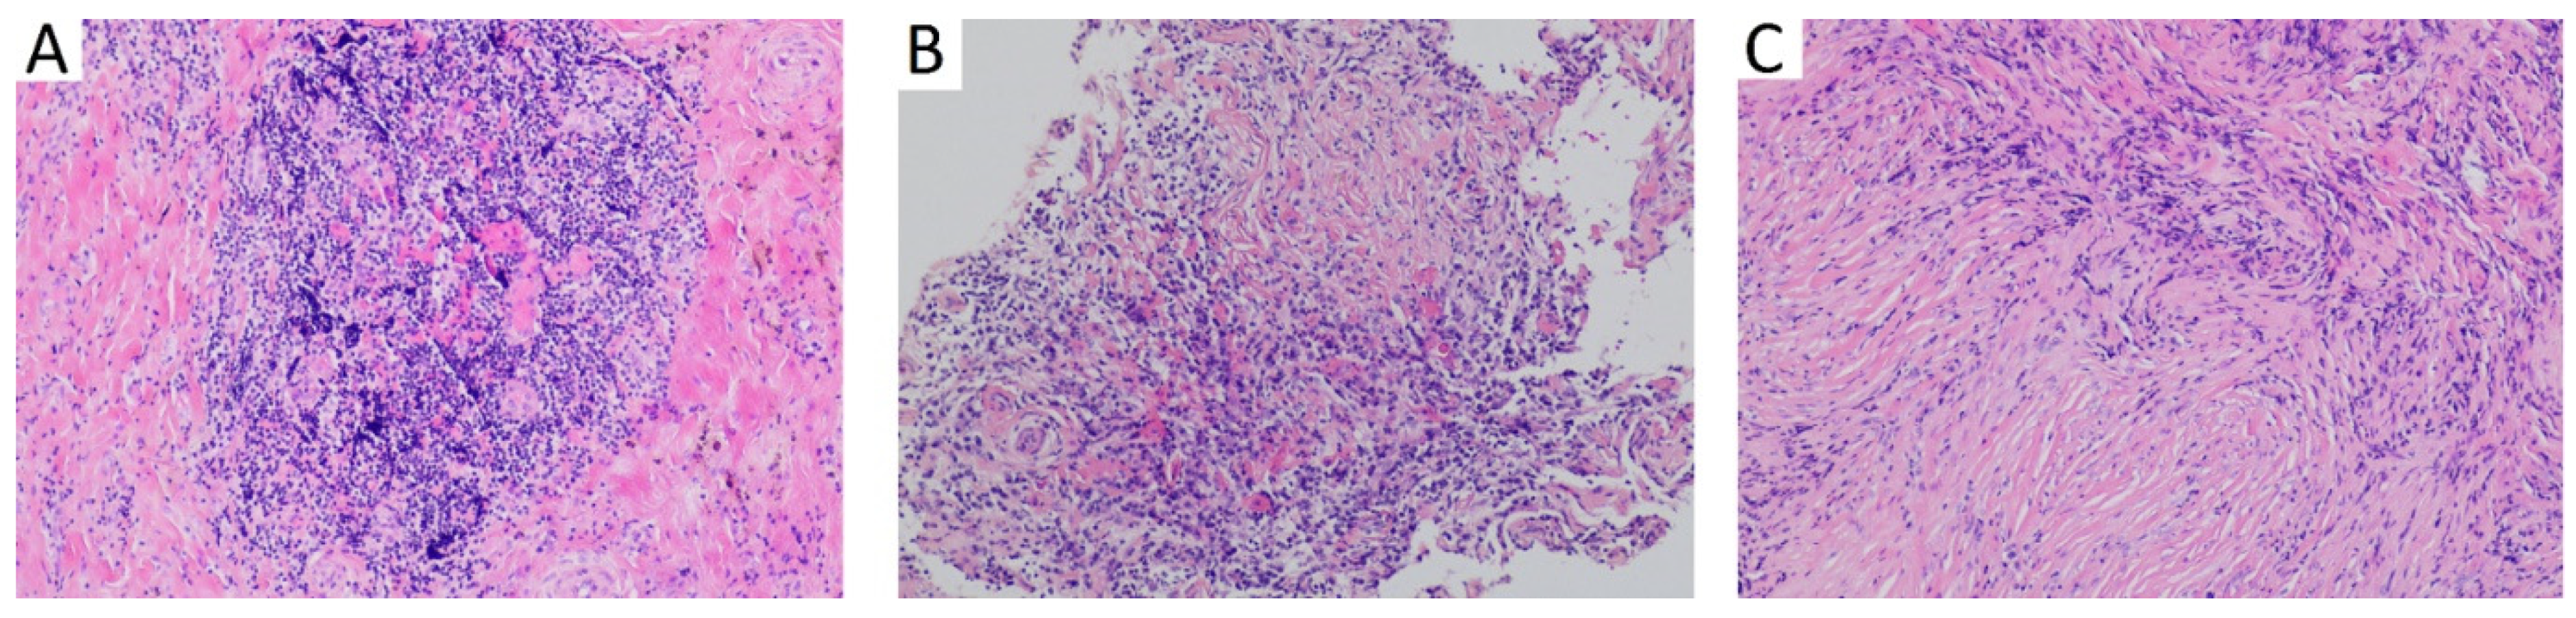

3.1. Case 1

| 18 | 2016 | Israel | Present study | 48 | m | otitis media with effusion | 1 | - | fibrous tissue with storiform fibrosis, lymphoplasmacytic infiltration, obliterative phlebitis | IgG4 positive 15 per HPF; IgG4:IgG < 20% | 210 mg/dL |